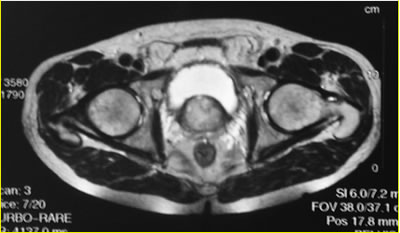

МРТ

таза